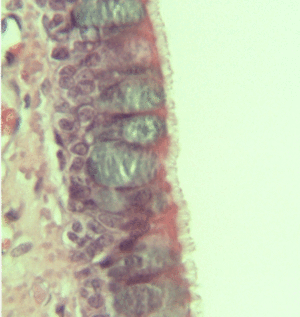

Illustration depicting Pseudostratified Ciliated Columnar Epithelium. | |

الطلائية العمودية المصففة الكاذبة Pseudo stratified Columnar Epithelium تكون هذه الطلائية من أكثر من طراز واحد من الخلايا ، فبعض هذه الخلايا طويلة ذات أسطح عريضة وقواعد نحيلة تتلامس مع الغلالة القاعدية ، والبعض الآخر من الخلايا لها عادة قواعد نحيلة ، وهي تنحشر بين خلايا الطراز الأول وترتكز أيضا على الغلالة القاعدية ، ولكنها لا تصل إلى سطح الطلائية. ويخلق إنتظام أنوية هذا الطراز في مستويات عدة إنطباعا كاذبا بأن هذا الطراز يتكون من أكثر من طبقة واحدة ، ولكنها في الحقيقة تتكون من طبقة واحدة من الخلايا.

يبطن هذا الطراز من الطلائية القنوات الإخراجية الكبيرة للغدد كما هو الحال في الغدة النكافية ، وهي تبطن أيضا الجزء العلوي من الوعاء الناقل ومجرى البول الذكري والبربخ.

يختص هذا الطراز من الطلائية بالحماية.